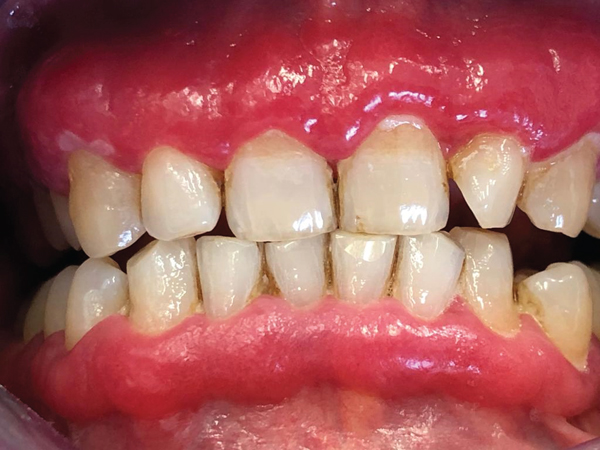

SCP-7202病人。

描述: SCP-7202是一种异常性的牙齿现象,其特征为突然出现温和但持续不断的牙龈瘙痒,无明确原因。截至目前,SCP-7202影响到Site-5331D内 70%左右的驻站居民以及40%的全天雇员。非异常环境及条件因素(如水质、个人卫生)已被排除。无论如何,患有SCP-7202的人员报告称若身处Site-5331D之外,症状烈度就会减轻。

描述: SCP-7202是一种急性的特发性难治牙龈炎1,自发影响着Site-5331D的驻站居民以及全天雇员。由于非全天雇员不受影响,以及有多名受影响雇员在被转移到其他基金会站点后报告症状减弱,确信SCP-7202的发展与在Site-5331D的停留时间相关。